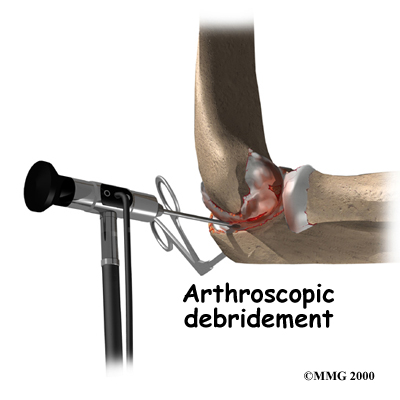

If you are in an early stage of OA, your doctor may recommend arthroscopic debridement. Other names for this procedure include arthroscopic ulnohumeral arthroplasty or osteocapsular arthroplasty.

If you are in an early stage of OA, your doctor may recommend arthroscopic debridement. Other names for this procedure include arthroscopic ulnohumeral arthroplasty or osteocapsular arthroplasty.

Arthroscopic procedures use an arthroscope, which is a tiny TV camera that is inserted into the joint through a very small incision. The arthroscope allows the surgeon to watch on a TV screen what he or she is doing inside the joint during the procedure.

In arthroscopic debridement, the surgeon makes other small incisions for inserting special tools to get rid of bone spurs, remove loose bodies, or to smooth the cartilage. Sometimes a capsular release is needed. An incision is made in the tissue and the anterior (front) of the capsule is removed.

Your surgeon may also do lavage of the joint. Lavage involves rinsing the joint with a sterile saltwater solution, which helps remove tiny debris that may be irritating the joint.

The majority of patients treated with arthroscopic debridement for elbow OA have less pain and more motion after surgery. Symptoms may come back in some patients, but they are usually less severe.